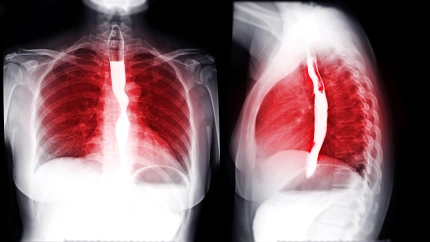

Cancer esófago

Imagen de archivo